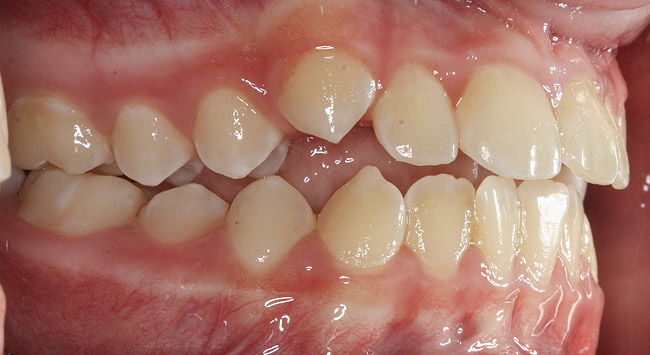

(4.) Patient presents bilateral crossbite and significant attrition. Father assists in retraction.

Figure 4